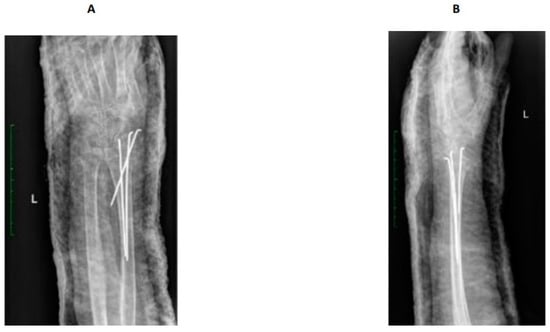

The patient came to the emergency department with intense pain, loss of function, and swelling in the left forearm following a fall from her a standing position onto a hard surface. A physical examination and X-ray of the left upper limb led to the diagnosis of a Colles fracture. The limb was realigned and secured in a plaster cast. After 28 days, surgery involving Kirschner wire stabilization of the radial bone was performed (Figure 1). Following hospital discharge, the patient underwent five outpatient follow-up visits, which included X-rays of the left upper limb and changes to the plaster cast. Notably, symptoms indicative of developing the complex regional pain syndrome (CRPS) remained unnoticed until the last control visit. During the seventh week post-surgery, an attempt to remove the Kirschner wires was made. However, due to the observation of troubling symptoms, the patient was subsequently referred to the Department of Rehabilitation and Orthopedics in March 2023.

Figure 1.

X-ray after surgery. Distal radius fracture of the left upper limb with K-wire. AP view (A), lateral -view (B).